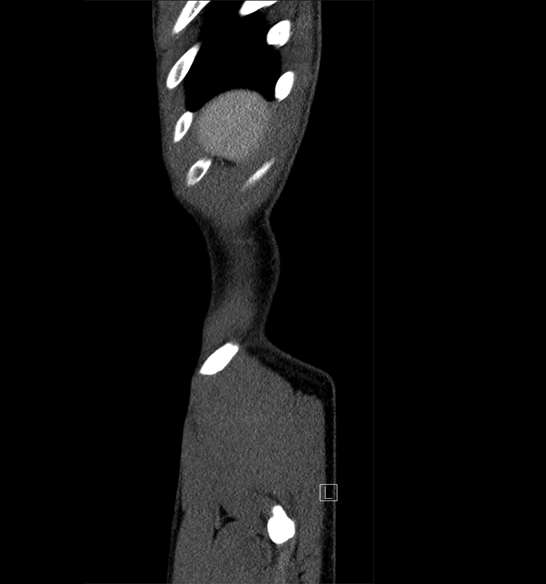

Body

Covers abdominal CT anatomy.